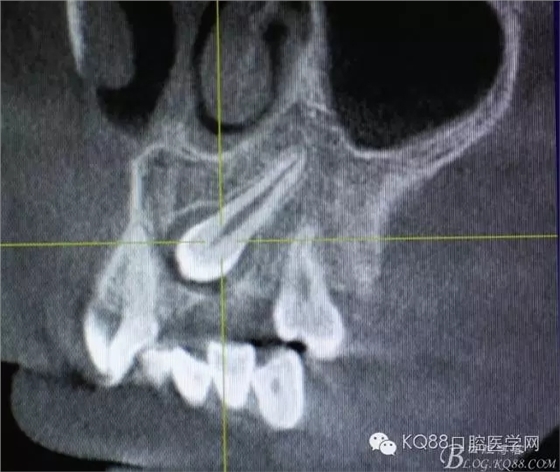

患者、王xx、男,17歲。主訴:牙齒排列不齊,要求治療。專(zhuān)科檢查:63乳牙滯留、22、23未萌出,cbct檢查:22牙冠畸形、過(guò)小牙,23高位埋伏阻生。正畸科治療計(jì)劃:拔除63、22,開(kāi)窗正畸牽引23。患者同意治療方案,簽知情同意書(shū),轉(zhuǎn)診外科,拔除63、22,并行23開(kāi)窗術(shù)+托槽粘接。

圖1.術(shù)前的cbct影像檢查:23位于腭側(cè)、牙齒位置比較高。